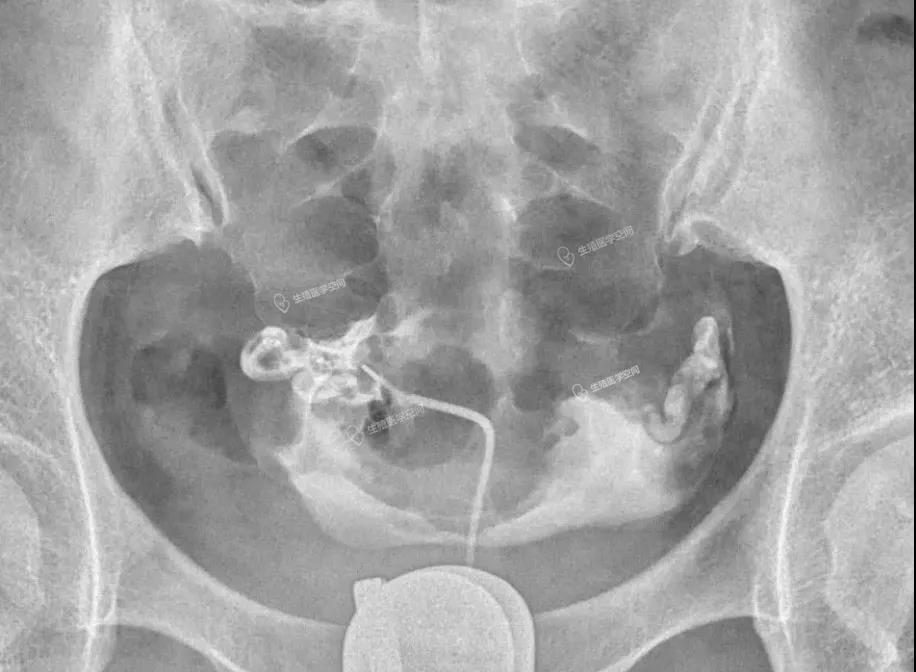

病例4 女 26岁 继发不孕,子宫输卵管造影发现双侧输卵管间质部阻塞。男方检查均正常。通过造影片初步评估介入再通术疏通成功率很高,可以达到90%左右,于是做放射科的介入再通术成功疏通了2侧输卵管。术后第5个月怀孕,后来足月妊娠,自然分娩一健康婴儿。